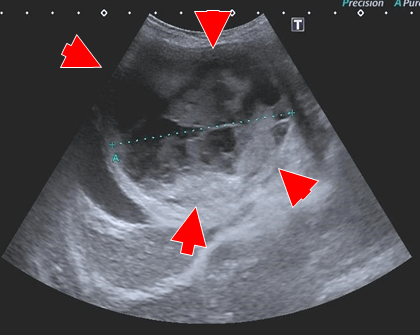

【各種検査所見】

血液検査

― 重度の貧血 (PCV16%)

― その他著変なし

レントゲン検査

― 上腹部領域に腫瘤陰影

腹部超音波検査

― 右上腹部に40mm大の腫瘤陰影

― 腹腔内に液体貯留

― 穿刺吸引→血様の液体

CT(第2病日)

肝動脈尾状葉枝が栄養血管門脈血の流入は確認されず

尾状葉由来5cm大

動脈相

門脈相

CT MIP

【診断・治療方針】

腹腔内腫瘤の破裂による非外傷性出血

― 腹腔内腫瘤は肝尾状葉由来 (Φ5cm)

腫瘤は動脈相で早期膿染

― 肝動脈尾状葉枝が栄養血管